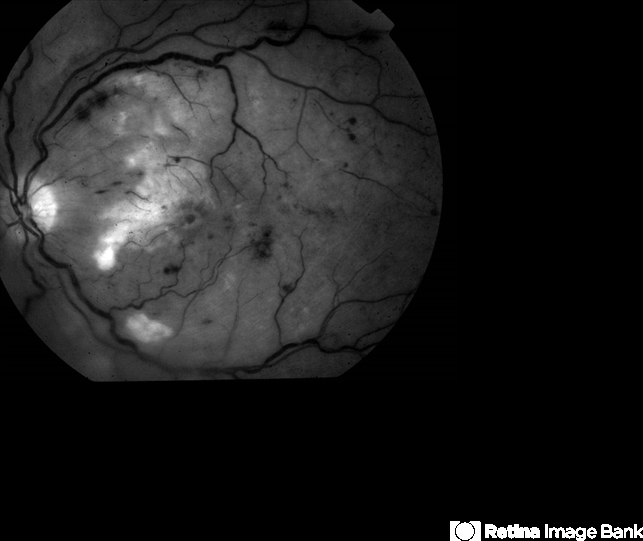

- partial arterial occlusion

- Fundus camera

- Red Free image of a 72-year-old man with sudden loss of vision shortly after a renal artery catheterization.